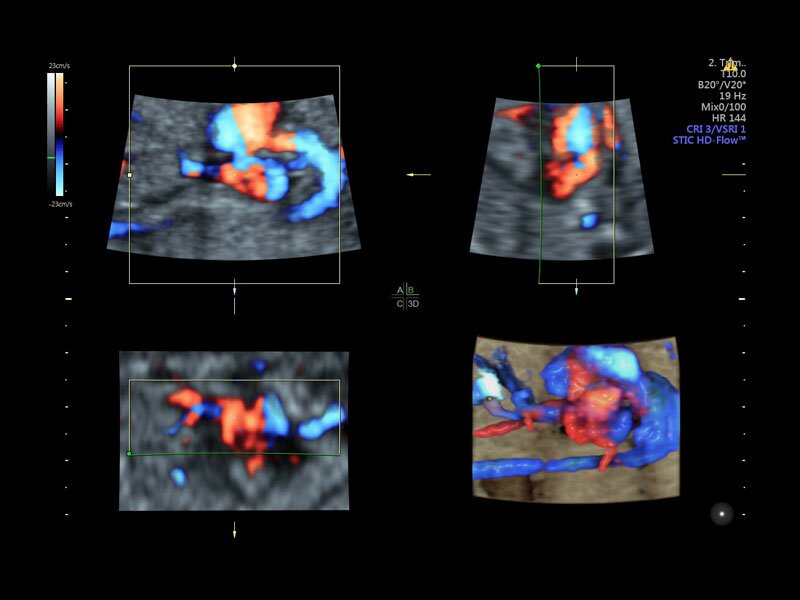

• Advanced STIC - расширенный программный пакет для исследования сердца плода в режиме 4D для механических и электронных объемных датчиков:

• Использование цветного, энергетического допплера, В Flow - режим STIC.

• Сочетание с М-режимом - STIC-M-Mode

• Перемещаемый источник света - STICflow

• SonoVCADHeart - программное обеспечение для исследования сердца плода в режиме 3D/4D (быстрый доступ к плоскостям сканирования) по рекомендациям ISUOG

• SonoVCAD heart (Sonography-based Volume Computer Aided Display heart) — программа формирует изображения сердца плода в стандартных проекциях в соответствии с международными рекомендациями на основе одного объемного изображения или данных 4D визуализации, полученных методом STIC.